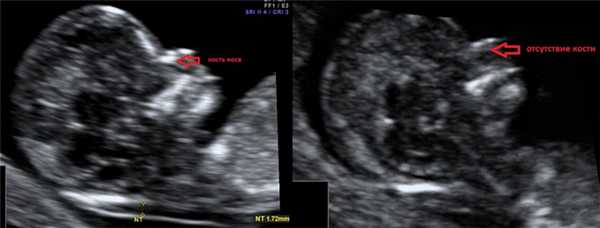

1. Увеличение ТВП.

Оценка этого параметра проводится в первое скрининговое УЗИ (11-14 недель)

ТВП (толщина воротникового пространства) может оказаться больше нормы по нескольким причинам.

Почему у плода может выявляться увеличение ТВП?

2. Гипоплазия\аплазия костей носа.

Гипоплазия костей носа - уменьшение размеров косточки носа в зависимости от КТР вашего малыша.

Аплазия костей носа - отсутствие визуализации косточки носа у вашего малыша.

Отсутствие видимости костной части спинки носа у плода или ее недоразвитие (недостаточно яркая) на первом скрининге связана с задержкой отложения кальция. Такая ситуация несколько чаще может встречаться у плодов с синдромом Дауна, однако важно, что:

- само по себе отсутствие костей носа на УЗИ не является аномалией развития; может встречаться у абсолютно здоровых плодов (в 3% случаев);

- для оценки степени индивидуального риска необходима оценка остальных ультразвуковых маркеров (толщина воротникового пространства плода, показатели кровотока на сердечном клапане, показатели кровотока в венозном протоке, ЧСС плода) и биохимического анализа материнской сыворотки (РАРР-А, ХГЧ);

- Если результат комбинированного скрининга (оценка в специальной программе данных УЗИ и анализа крови) показывает НИЗКИЙ риск хромосомной патологии - беспокоиться не стоит. Обязательно пройдите контрольное УЗИ в 19-20 недель беременности, где будет проведена тщательная оценка анатомии плода и исследованы определенные ультразвуковые маркеры второго триместра беременности.

- Что делать если результат комбинированного скрининга оказался ВЫСОКИМ? - Переживать не стоит. Вас обязательно направят на консультацию к врачу генетику, который собрав анамнез, оценив все риски, даст рекомендации по дополнительным методам исследования (инвазивная диагностика).